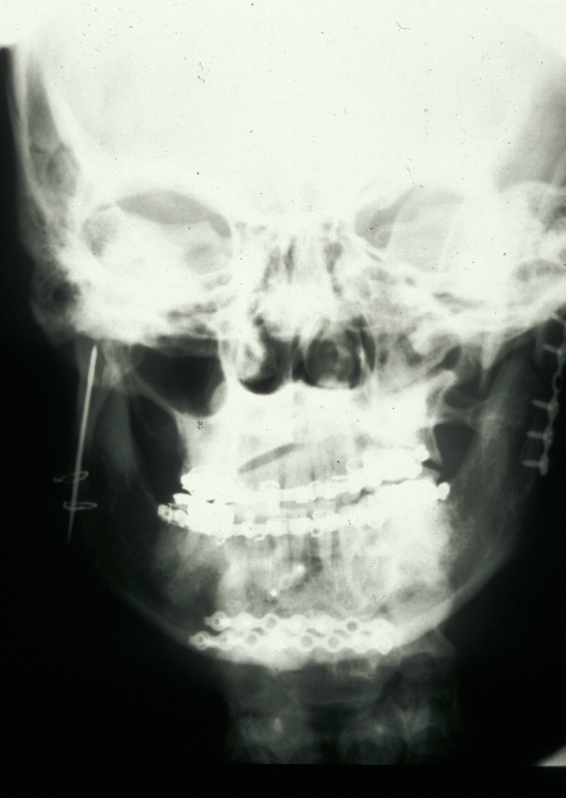

In the region of the angle of the mandible, a single plate is adequate to allow healing. In practice many surgeons now supplement this (or even replace it) with a transbuccally placed lateral plate which prevents lateral displacement of the lower border of the mandible. All these techniques use monocortically placed matching titanium screws to retain the plates which immobilise the fracture sites. Long-acting local anaesthetic regional block provides good postoperative analgesia and prophylactic broad-spectrum antibiotics are given preoperatively. Intraoral wounds are closed with resorbable sutures. If the occlusion is fully restored and stability of the fracture is assured by the plates, the intermaxillary fixation can be removed. Postoperative radiographs are taken to ensure correct placement of plates and screws and accurate realignment of mandibular fragments. It is also important to reassess the position of the condyles following ORIF as malpositioning can lead to TMJ problems later on (see Figure 5).